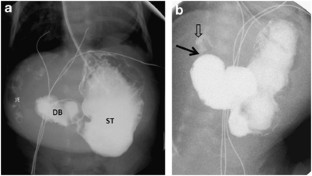

Herman, T., Siegel, M. Giant omphalocele, intrinsic duodenal obstruction. J Perinatol 31, 293–295 (2011). https://doi.org/10.1038/jp.2010.163